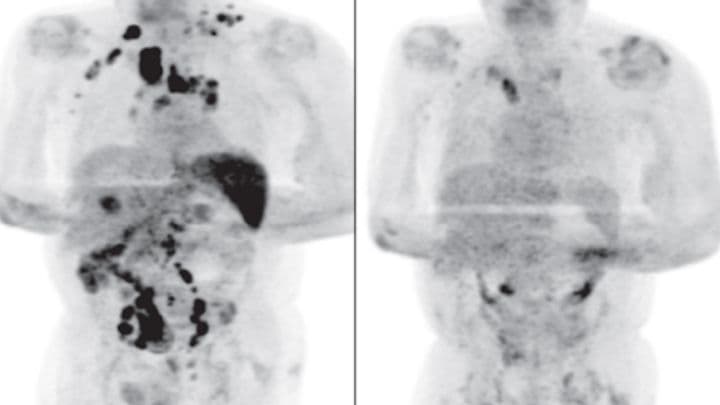

Se trata de un hombre de unos 40 años que, antes de padecer Covid-19, había pasado por un tratamiento agresivo contra el cáncer, lo que había dejado su sistema inmunológico bastante debilitado, señaló la Fundación de Amparo a la Pesquisa del Estado de Sao Paulo en Brasil.